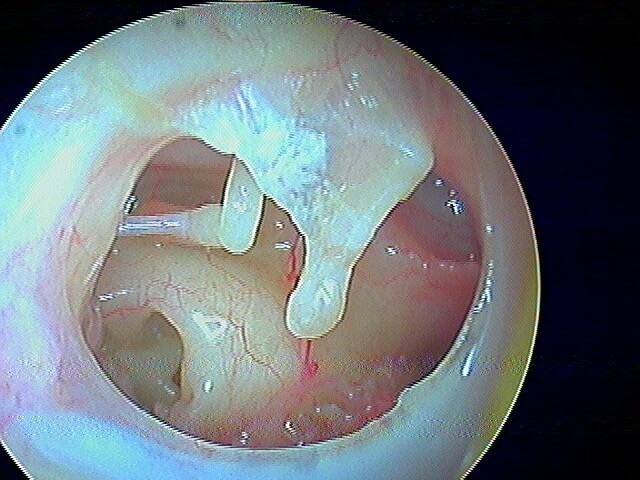

Rare le cholestéatome du CAE, le tympan étant normal. Le diagnostic otoscopique est posé par la présence de squames et d'érosion osseuse. Ce sont des patients qui font des otites externes très rapprochées.

Post-opératoire à 1 an (le cadre osseux s'est reconstitué seul, j'avais juste fraisé):